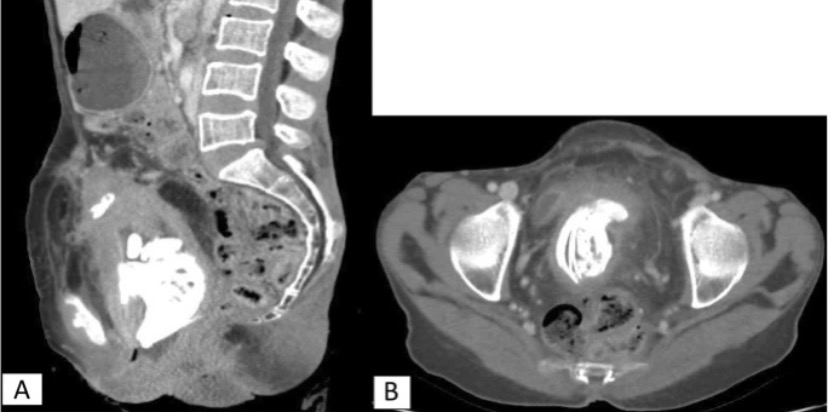

Фото 2

НемедицинаПостконтрастные изображения компьютерной томографии брюшной полости. а. Сагиттальное изображение, показывающее внутриутробные костные части плода и очаговое прилипание матки к передней брюшной стенке. б. Осевое изображение, показывающее множественные костные структуры плода и смещенный мочевой пузырь